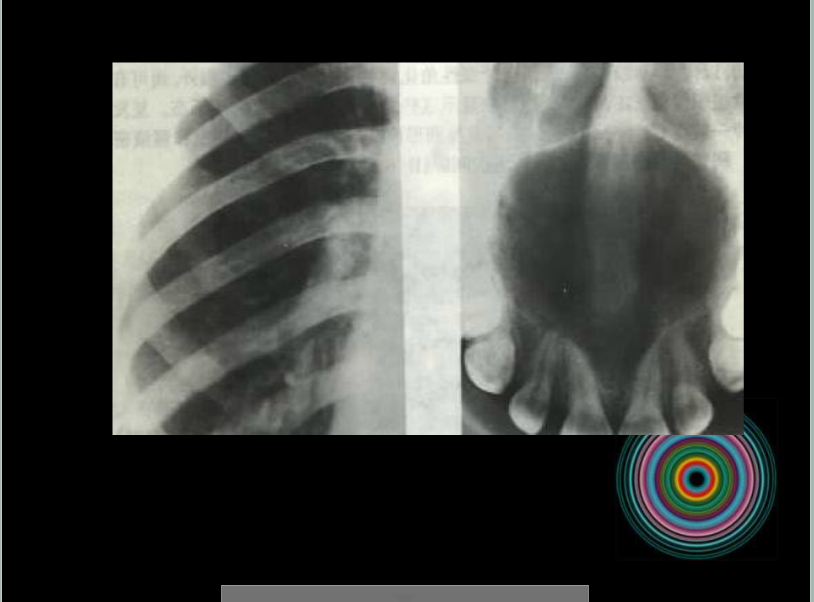

口腔頜面外科 影像技術(shù)